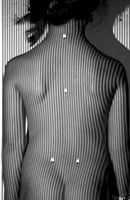

Возможность использования топографического мониторинга состояния больных сколиозом взамен рентгена была изучена на основе клинического материала школы-интерната №133 для детей больных сколиозом г.Новосибирска, где, начиная с 1995 года, проводились ежегодные обследования на ТОДП постоянного контингента больных параллельно с рентгеном. Среди больных по характеру течения заболевания выделены 3 группы: СФ - стабильная форма сколиоза, УПФ - умеренно прогрессирующая, БПФ - быстро прогрессирующая форма. Пример наблюдения больной с быстро прогрессирующей формой сколиоза приведен на рисунках ниже.

9,0 лет 10,4 лет 10,8 лет 11,4 лет 12 лет

PTI=1,0; Cobb=10° PTI=1,3; Cobb=17° PTI=1,9; Cobb=23° PTI=2,9; Cobb=38° PTI=3,6; Cobb=55°

За трехлетний период наблюдения в возрасте с 9 до 12 лет основная правосторонняя грудная дуга по углу Кобба спрогрессировала с 10 до 55°, т.е. средняя скорость прогрессирования составила 15° в год. Общий индекс нарушения формы дорсальной поверхности туловища PTI изменился с 1,0 (граница нормы и умеренно выраженных отклонений) до 3,6 (значительное отклонение). Следует обратить внимание, что в начале наблюдения туловище больной имело хороший баланс во фронтальной плоскости (вертикальная ось, проходящая через вершину межъягодичной складки, проходит также и через C7), а с возраста 10,8 лет стало явно нарастать нарушение баланса с отклонением туловища вправо, т.е. в сторону выпуклости основной дуги. Приведенный пример убедительно демонстрирует наглядность топографических данных и их большую информативность для решения задачи неинвазивного мониторинга состояния больных сколиозом.